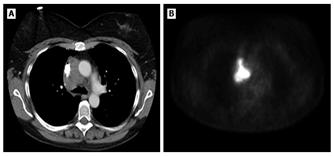

Figura 8.

(A) Una radiografía de tórax muestra una clavícula derecha rota con un gran neumotórax derecho y neumomediastino en una mujer de 24 años atropellada por un automóvil. (B) Una radiografía obtenida después de la colocación de un tubo torácico muestra un neumotórax persistente. Se observó una gran fuga de aire del tubo. La broncoscopia reveló una rotura completa del bronquio principal derecho